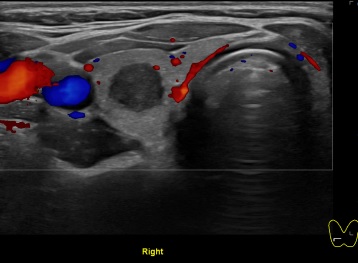

상기환자 외부건강검진이상소견으로 세침검사위해 내원하신 20대후반 여성분으로

의심스러운 갑상선 우엽 결절 세포검사 진행후 갑상선암으로 진단되었습니다